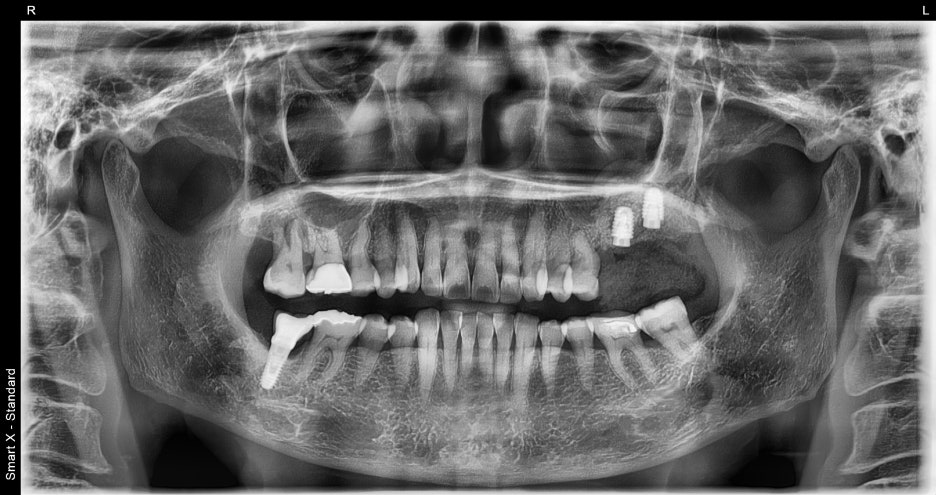

3.치유 기간 후 보철(크라운) 장착

① 발치 및 임플란트 식립

– 부러진 치아를 발치한 뒤, 골 상태가 안정적이어서

같은 날 바로 임플란트를 심을 수 있었습니다.

③ 보철물 제작 및 장착

– 치과 내 기공소에서 환자분의 다른 치아 색상과

어울리도록 맞춤 지르코니아 크라운을 제작했습니다.

– 교합(물림)을 조정하여 자연스럽고

편안하게 씹을 수 있도록 장착했습니다.

1회차: 발치 + 임플란트 2개 동시 식립

최종: 맞춤 크라운 장착 → 정상적인 저작 회복

치료 전 후 사진